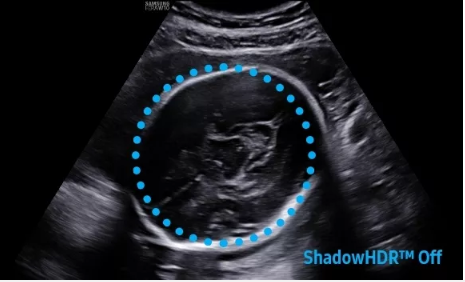

2D成像方面,Hera i10集成了包括ShadowHDR?、HQ-Vision?、ClearVision等多項具有三星“血統(tǒng)”的技術,加強了圖像的陰影抑制、減少偽影、緩和模糊區(qū)。